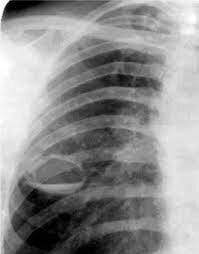

Золотым стандартом в диагностике фиброзно-кавернозного туберкулеза является рентген. На снимке можно обнаружить следующие признаки:

1. Появление каверн – полостей неправильной формы с размытыми контурами;

2. Обнаружение фиброзного перерождения ткани легких вокруг кавернозных очагов;

3. Уменьшение расстояния между ребрами, которое заметно на рентгеновском снимке;

4. Смещение органов средостения (пищевода, трахеи и других) в сторону поврежденных тканей;

5. Деформация и смещение корней легких.

При наличии острого процесса рентген поможет обнаружить новые полости некротического распада, которые по контуру окружены воспалительным процессом, также заметным на снимке.